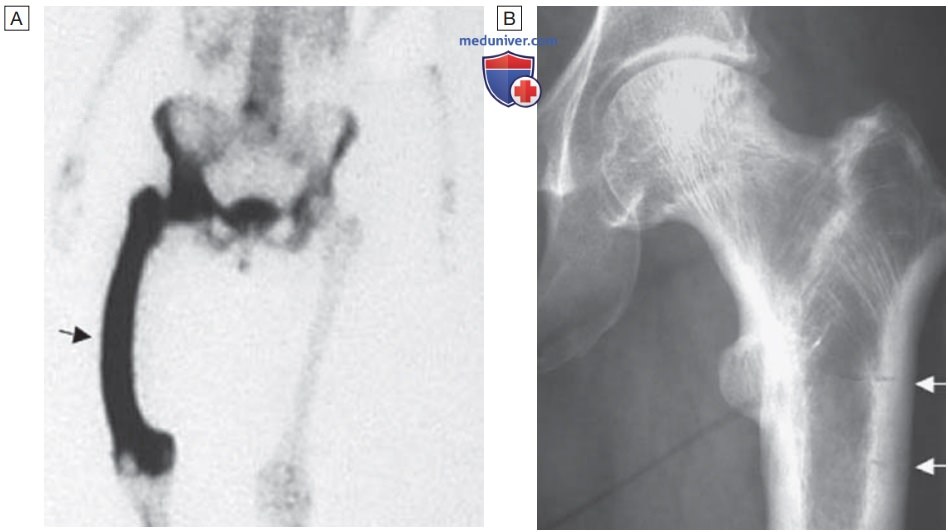

Рентгеновские снимки и визуализация болезни Педжета

Раздел: Мудрость в объективе